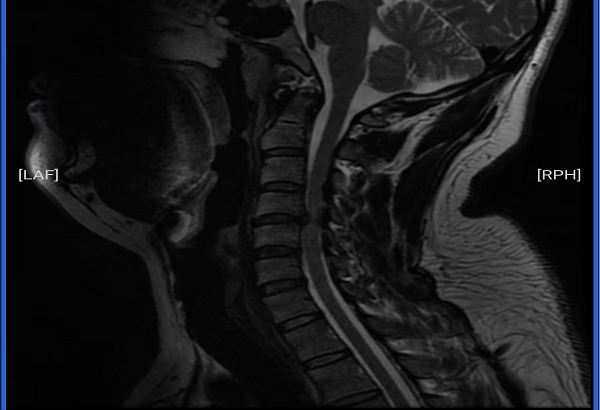

术前核磁检查